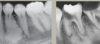

What is this radiographical finding?

Metastatic Carcinoma to Jaw Bones

C. Periapical image of a metastatic lesion of breast carcinoma; note the irregular widening of the periodontal membrane spaces and patchy sclerotic bone reaction, especially around the roots of the molars